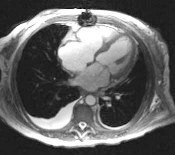

Aortna insuficijencijaU akutnoj aortnoj insuficijenciji zbog nemogucnosti adaptacije LK, UV pada uz dramaticno visok enddijastolni pritisak (I preko 40 mmHg)U ch. AI efektivni UV i EF su normalni / neznatno smanjeni i u miru i pri naporu.EF LK odrzava se normalnom cak i kada pocne depresija miokardne funkcije (procenjena na osnovu nagiba krive ESP/ESV kao najosetljivijeg funkcionalnog pokazatelja). Sa napredovanjem disfunkcije LK , EF pri naporu pada,a ESV raste I bez dodatnog povecanja RV.ESV se uzima kao sveukupan indeks miokardna funkcije LK I dobro korelise sa operativnim mortalitetom I sa dugorocnom prognozom.Ishod je bolji ako je ESV manje od 40ml/m2 ,a los ako je ESV veci od 80ml/m2.Umesto ESV mnogo cesce se ehokardiografski odredjuje ESD LK.Granicna vrednost u pogledu reverzibilnosti disfunkcije LK je ESD najvise 5,5 cm.